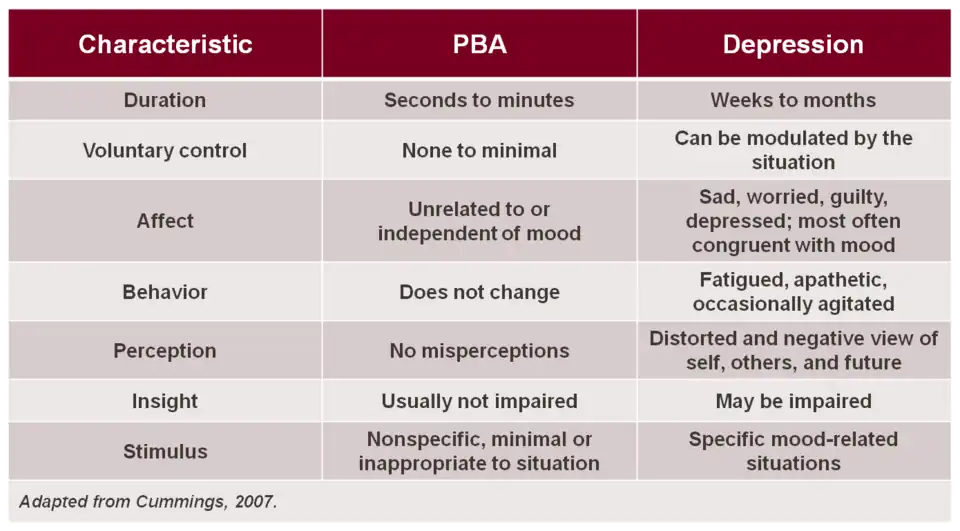

Pseudobulbar affect

Pseudobulbar affect (PBA) is an affective disinhibition syndrome that is largely unrecognized in clinical settings and thus often untreated due to ignorance of the clinical manifestations of the disorder; it may be misdiagnosed as depression.[77] It often occurs secondary to various neurodegenerative diseases such as amyotrophic lateral sclerosis, and also can result from head trauma. PBA is characterized by involuntary and inappropriate outbursts of laughter and/or crying. PBA has a high prevalence rate with estimates of 1.5–2 million cases in the United States alone.[78]